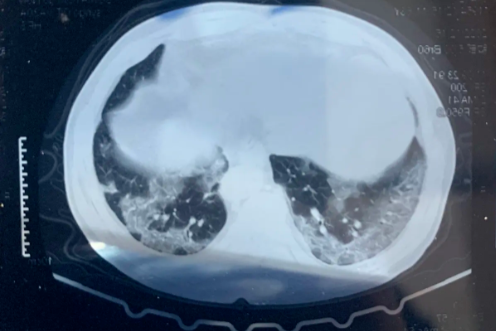

阜康医院呼吸内科提示:这份呼吸道传染病防控健康提示,请收好!